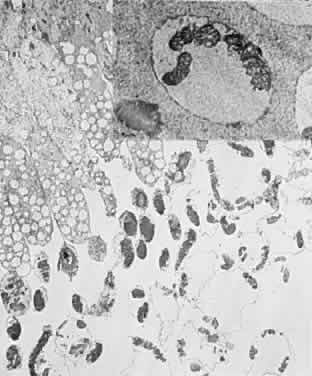

Clinicopathologic correlations of photic retinopathy have been reported by several investigators.16,75,76,144–146 Aware of prior studies by others on rats,25,147–150, Tso and coauthors reported the first of their series, performed on monkeys in 1972.75 They believed that the difference in their observations versus those published on rats might be related to the species of animal studied. Tso and coworkers created a model of chronic photic maculopathy through exposure to an indirect ophthalmoscope and found that significant changes were produced the first week after exposure, but a distinct maculopathy became evident only after an extended follow-up (5 months). They also described three stages in which this maculopathy occurs: initial degeneration in the first week, macrophagic response between the first week and first month, and repair and regeneration between the first and fifth month. Tso and associates also noted that, in the reparative phase, scarlike lesions noted clinically corresponded to proliferation of the RPE on a cellular level and, despite changes in the RPE, the overlying photoreceptors had regenerated. These clinicopathologic correlations led to more studies of macular response to light-induced injury. Histopathologic study of photic retinopathy in the human eye caused by exposure to light from the operating room microscope was reported by Green and Robertson in 1991.144 They describe the light and electron microscope findings of operating room microscope-induced maculopathy in a patient's eye after exposure to the light source for 60 minutes, 72 hours before enucleation for an iris melanoma (Figs 5 through 8). Findings in this acute form of photic retinopathy occurred mainly at the level of the RPE and photoreceptor layer and included the following: localized necrosis of the RPE; loss of the apical villi, plasma membranes, and cytoplasmic organelles of the RPE cells; extrusion of the retinal pigment epithelial pigment granules; and extensive disruption of the outer lamellae of the photoreceptors. Swollen mitochondria were present within the photoreceptor inner segments. Although this study was designed to address the issue of acute light-induced retinal damage, the additional finding of thinned retinal pigment epithelial cells, which apparently had migrated under injured RPE cells, suggests that a reparative process had already begun. The findings of Green and Robertson are consistent with those of Jaffe and coworkers reported in primates.146

Fig. 5. Light-microscopic appearance of an area of junction between phototoxic lesion (to the right) and normal unaffected retina and retinal pigment epithelium (to the left). In the lesion, the retina is edematous. An amorphous material is observed in the area of disrupted outer segements of the photoreceptors and the subretinal space. (Green WR, Robertson DM: Pathologic findings of photic retinopathy in the human eye. Am J Ophthalmol 112:520, 1991)

Fig. 6. Light-microscopic appearance of photic retinopathy with edematous outer retina and the edematous irregularly thickened retinal pigment epithelium. Most of the swelling involves the photoreceptor layer where an amorphous material largely replaces the outer segments. The photoreceptor nuclei appear relatively intact. (Green WR, Robertson DM: Pathologic findings of photic retinopathy in the human eye. Am J Ophthalmol 112:520, 1991)